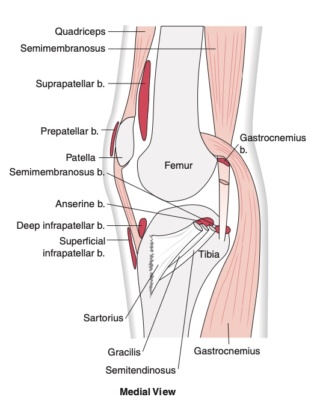

Các cấu trúc tạo thuận quanh khớp

Để tạo thuận sự vận động của khớp và các gân cơ, xung quanh gối có nhiều túi thanh dịch, như túi thanh dịch các cơ chân ngỗng, túi thanh dịch trên xương bánh chè, trước xương bánh chè, dưới xương bánh chè nông và sâu, túi thanh dịch ở hố khoeo…